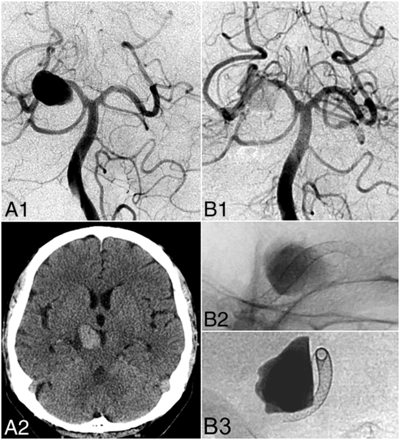

Illustrative case (patient 4). A 68-year-old man presented with right oculomotor nerve palsy. DSA (A1) and noncontrast head CT (A2) reveal a fusiform P2 aneurysm with a maximum diameter of 23 mm and a 7-mm length of the arterial segment involved (neck width). Endovascular reconstruction with 2 overlapping PED devices (2.5 × 20 mm, 2.75 ×10 mm) led to considerable stasis of contrast in the aneurysm body illustrated on postembolization control DSA (B1) and unsubtracted angiography (B2 and B3).

In the same patient, at 6 months, DSA shows complete angiographic aneurysm occlusion (C1). Regression of mass effect–related symptoms (CN III palsy) is correlated with the regression of aneurysm mass effect as illustrated on 6-month follow-up noncontrast head CT (C2). At 1 year, DSA (D1) confirms stable angiographic cure, and axial T2-weighted MR imaging (D2) shows nearly complete involution of the aneurysm sac.